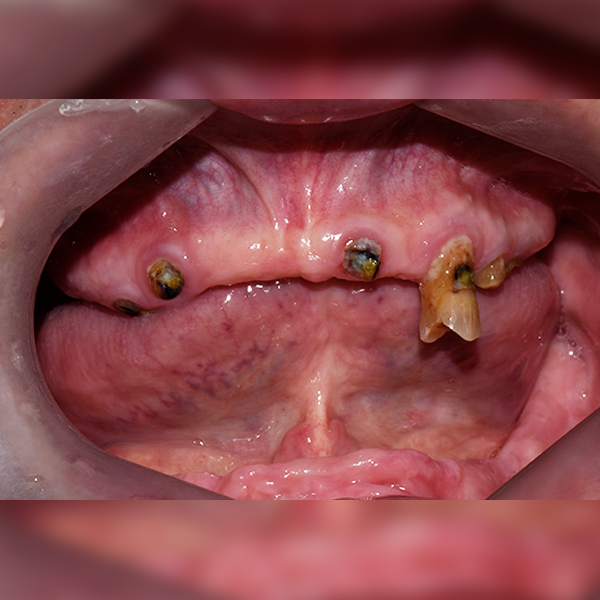

全顎/全体 / 骨移植|睡眠|高血圧|糖尿病

症例.56 70代 チョン*ジュ 2018-04-05 / 2018-11-08